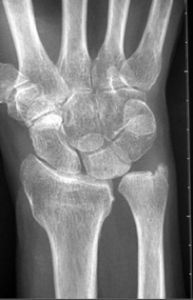

Cận lâm sàng

MRI là phương pháp chính xác, an toàn được sử dụng để xác định chẩn đoán. Trong khi đó, Xquang là phương tiện đánh giá ban đầu tốt để chẩn đoán gãy xương có liên quan.

Nội soi khớp cổ tay là tiêu chuẩn vàng để chẩn đoán, cho phép quan sát trực tiếp và điều trị ngay lập tức. [1]